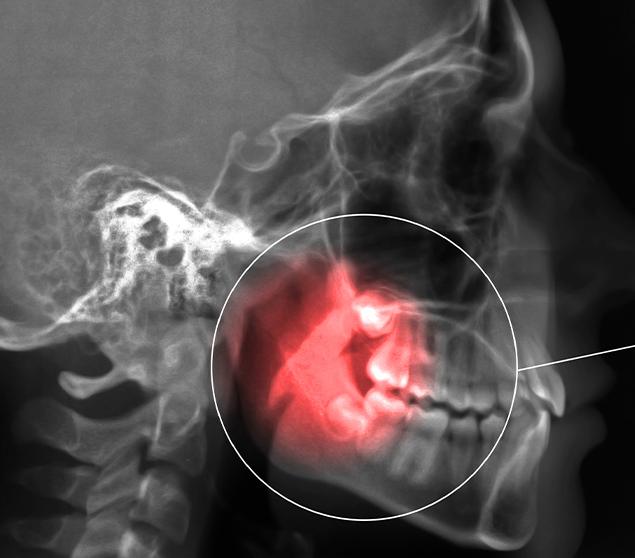

Before recommending extraction, our dental team completes a thorough assessment, which may include a clinical examination and dental X-rays. Findings and treatment options are reviewed clearly so you can make informed decisions about your care.